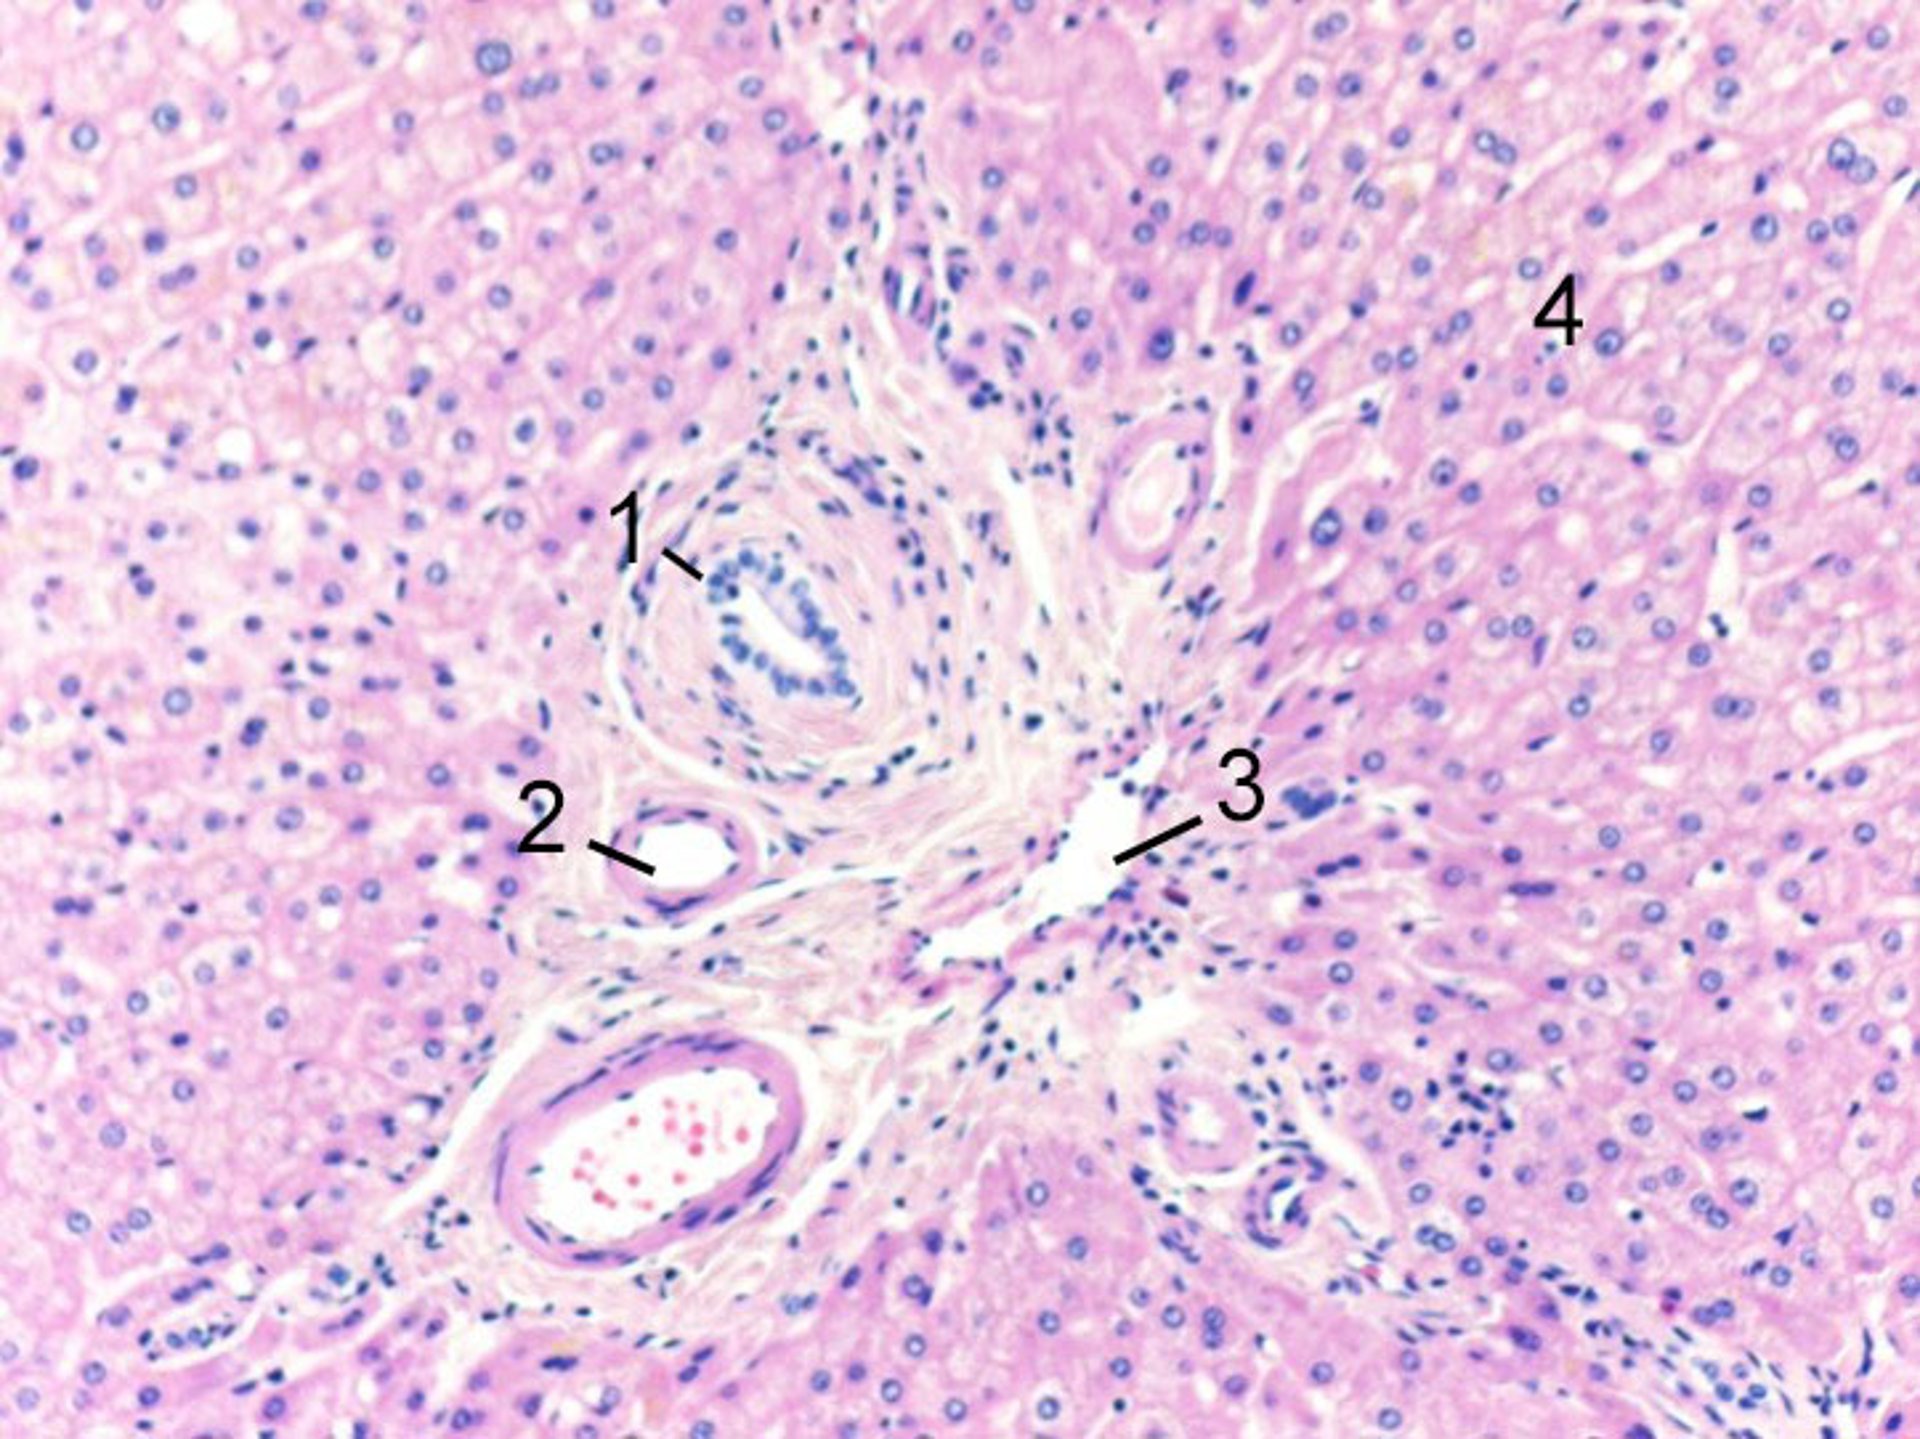

Bile salts (bile acids) are the major organic component in bile. Hepatocytes use active transport to secrete bile salts into the canaliculi, the channels between adjacent cells. Canalicular transport is the rate-limiting step in bile formation. Once secreted, bile salts draw other bile components (particularly sodium and water) into the canaliculus by osmosis. Bile salts are also biologic detergents that enable the body to excrete cholesterol and potentially toxic compounds (eg, bilirubin, drug metabolites). The function of bile salts in the duodenum is to solubilize ingested fat and fat-soluble vitamins, facilitating their digestion and absorption. From the canaliculi, bile flows into the intrahepatic collecting system, then into the right or left hepatic duct, and finally into the common hepatic duct.